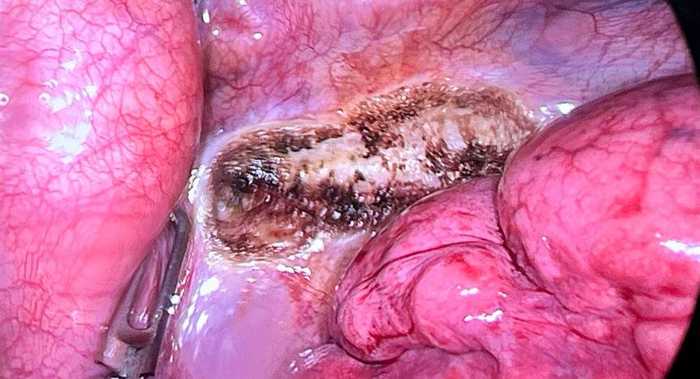

絕大多數患者手汗癥狀不會復發”通過充分的評估與準備,手術順利進行雙側手術在同一時段完成,雙側切口僅為1cm,無需引流管和尿管術后,小趙的雙手即恢復了干燥,且第二天順利出院,恢復良好小趙的康復經歷為其他面臨同樣困擾的青少年患者帶來了希望,他的勇敢選擇也為大家提供了有效的治療路徑。

胸部1cm切口常浩主任指出,交感神經鏈切斷術是一項成熟且常見的手術方式,通過對交感神經鏈進行切除或阻斷,成功減輕了大多數手汗癥患者的癥狀該手術因其創傷小、恢復快、效果顯著,成為治療原發性手汗癥的首選方法之一。